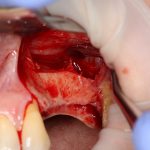

Кстати, обрати внимание на ширину альвеолярного гребня (левая картинка). Она чуть меньше 3 мм. Это объясняет, почему я засомневался в возможности установки имплантатов одновременно с остеопластикой. Понятно и без КЛКТ.

Наперво, мне нужно удалить разрушенный зуб и получить костный аутотрансплантат.